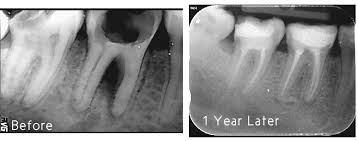

Root Canal Special Case Study

At Rehan Dental Surgery we do root canal treatments in the best possible manner and with proper protocols. We strive to attain reliable results by doing root canals in the same manner as done across the world. We educate our patients that your tooth is more worthy than most expensive diamond in the world and by root canal treatment majority of your teeth can be saved. Root canal is one of the most complicated treatments and needs rigorous training as every tooth has a hidden surprise inside it and only a specialist is able to manage such complexities as he is trained for it. Below is a case of root canal treatment of maxillary 2 premolar done by our specialist. This type of case was reported only 1-6% times in the whole world. Our specialist managed this case with perfection.